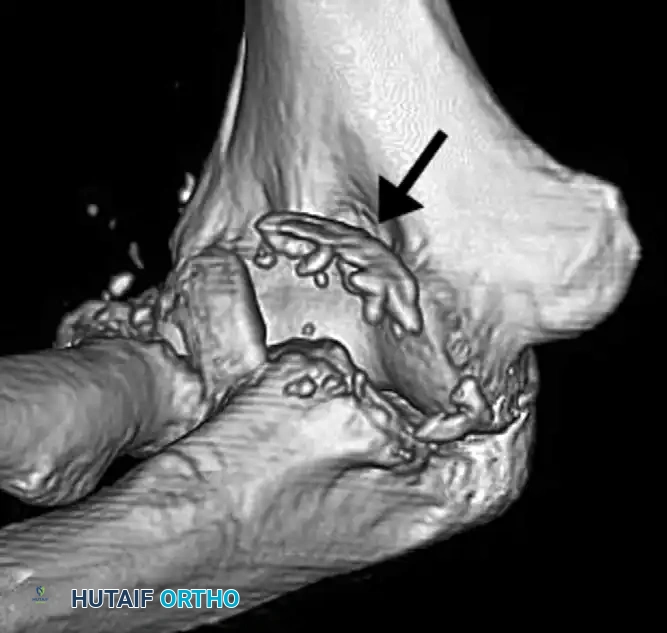

More recently, the classification system developed by O’Driscoll et al. has superseded the Regan and Morrey system. Based on three-dimensional computed tomography (3D CT), this system more reliably predicts associated capsuloligamentous injuries, pathomechanics, and guides precise treatment decisions.

Clinical Pearl: Because a coronoid fracture fragment may appear deceptively small on a standard lateral radiograph, or may be obscured by or confused with a radial head fracture, a CT scan with 3D reconstructions is strictly recommended whenever a coronoid fracture is suspected.

Standard anteroposterior (AP) and lateral radiographs are the first line of imaging. The "double crescent sign" on a lateral radiograph is pathognomonic for an anteromedial facet fracture. However, radiographs alone are insufficient for surgical planning. 3D CT is mandatory to identify all components of the injury, delineate the fracture morphology, and template for internal fixation.

A distinct type of coronoid fracture, the fracture of the anteromedial facet, occurs from a varus force to the elbow combined with an axial load. This mechanism shears off the anteromedial rim of the coronoid and invariably ruptures the lateral collateral ligament (LCL) complex.

If left untreated, this injury results in posteromedial rotatory instability (PMRI). The ulna subluxates posteromedially, leading to rapid, catastrophic wear of the medial radiocapitellar joint and ulnohumeral arthrosis.

Treatment necessitates an aggressive surgical approach. Repair of the lateral collateral ligament and Open Reduction and Internal Fixation (ORIF) of the coronoid are strictly recommended. Fixation is best achieved using a contoured anteromedial buttress plate applied through a medial approach, supporting the fragment against the varus shear forces.